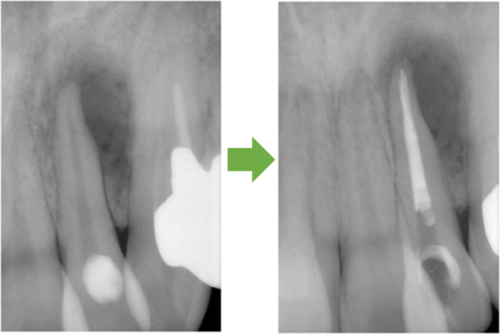

歯髄壊死 右上の前歯 川口の歯科 歯医者 さかえ歯科クリニック

2014年12月16日

術 前 術 後